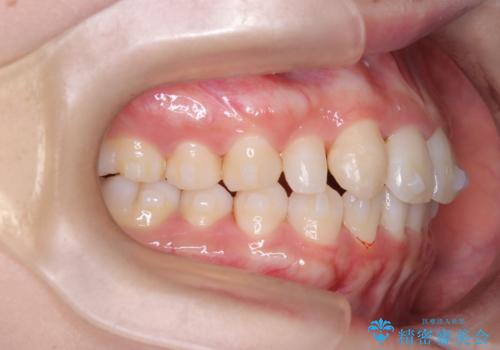

【インビザライン】八重歯が気になる

- 乳歯を抜歯してスペースを確保し八重歯の改善を行いました。

インビザラインをしっかり使用していただいたので、きれいな歯並びになりました。